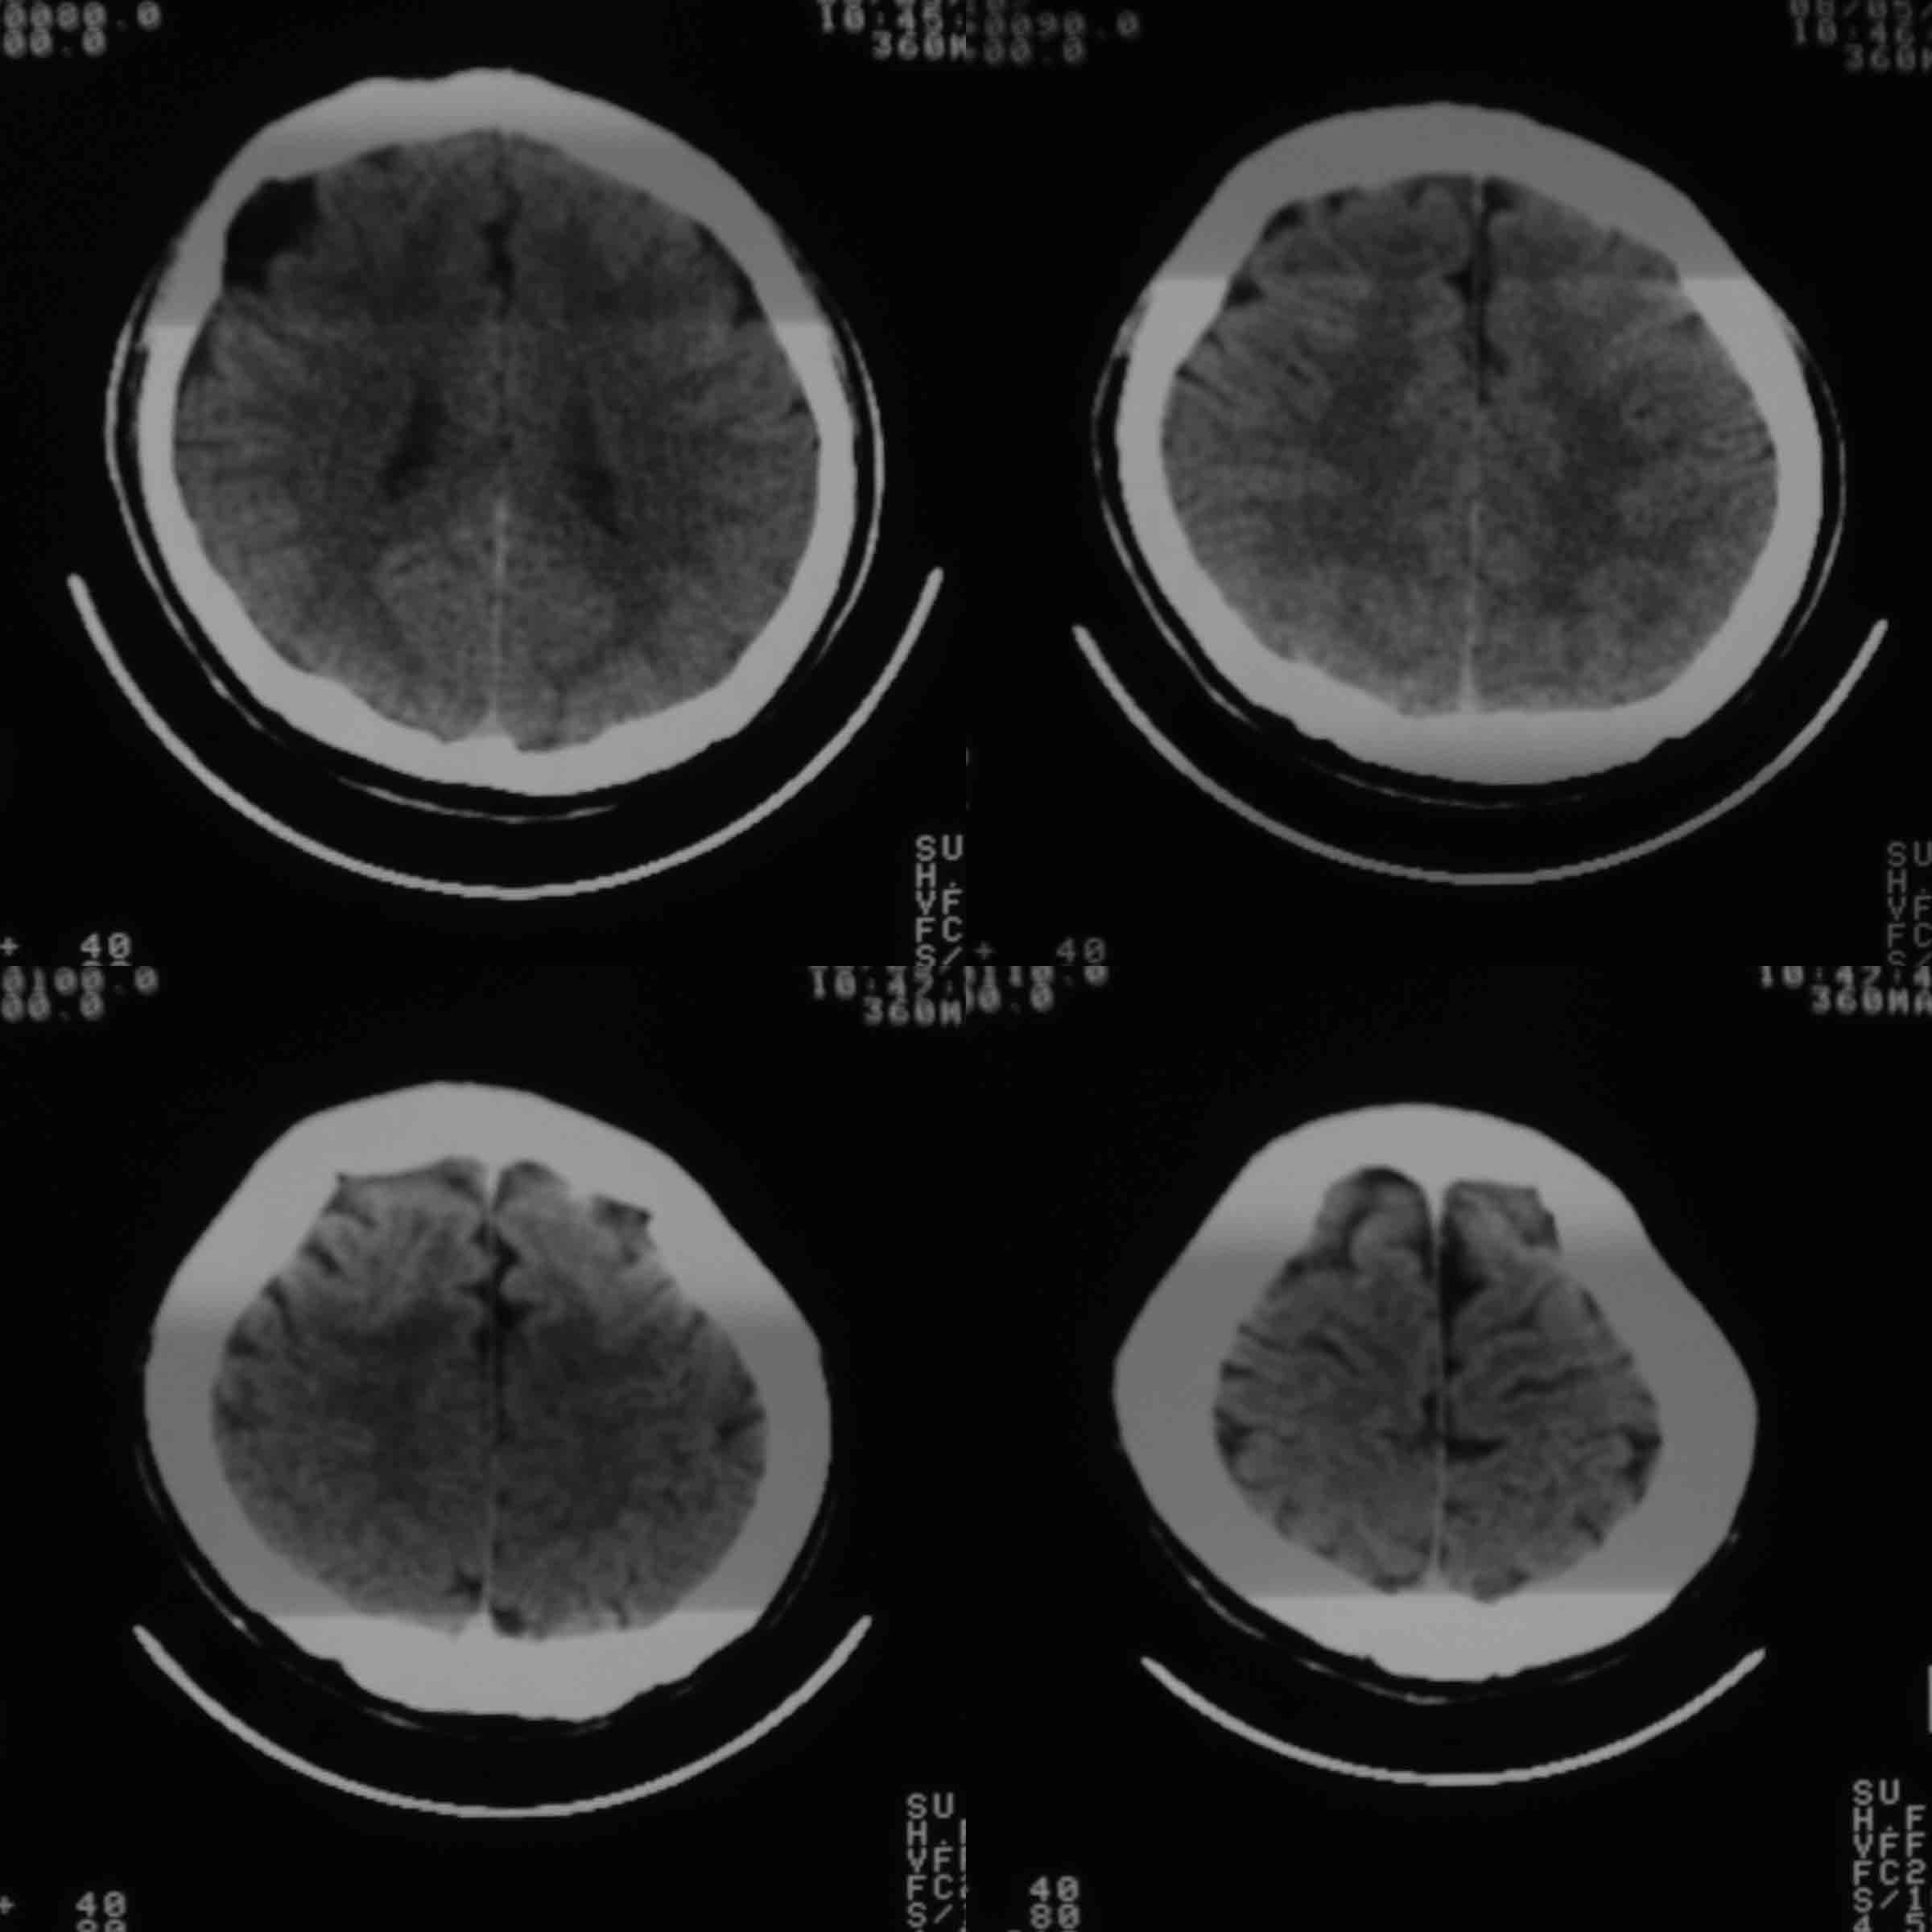

男37岁头持续性痛1天。右额部蛛网膜下腔囊肿诊断是否正确,请老师们帮忙看看。谢谢!

支持右额区蛛网膜囊肿。

有顶叶蛛网膜下腔囊肿

右侧额叶蛛网膜囊肿。